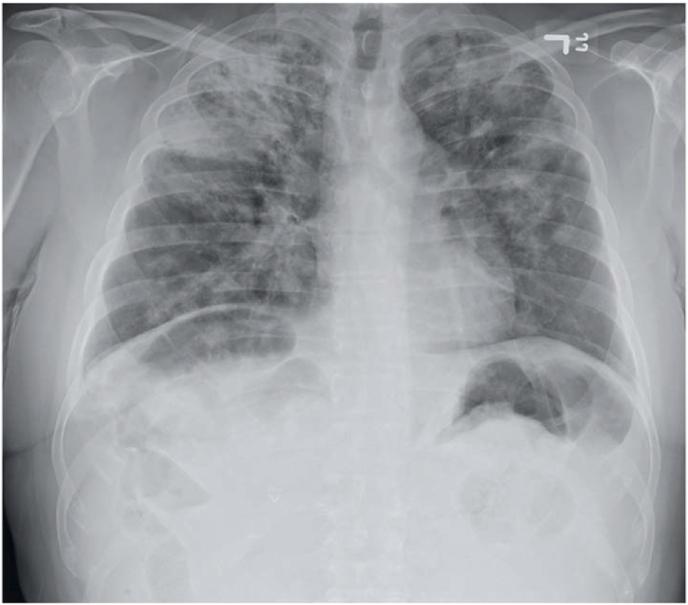

The SARS-CoV-2 infection has been found to present with different degrees of response and variable levels of inflammation. Patients who have recovered from the initial infection can develop long-term symptomatology. We present a unique case of a middle aged-healthy man who developed complications of ANCA-associated vasculitis after recovering from a mild COVID-19 infection. A previously healthy 53-year-old male presented with hemoptysis and acute renal failure. One month prior, the patient tested positive for COVID-19; not requiring hospitalization. Physical exam findings included bilateral lower extremity petechiae. CT Chest showed bilateral diffuse patchy lung consolidations with cavitary lesions with urinalysis revealing erythrocytes, +1 protein. Hemodialysis and workup for pulmonary-renal syndromes were initiated. Infectious workup results included: negative COVID-19, negative MTB-PCR, respiratory culture revealing yeast. Additional workup revealed; elevated CRP, D-Dimer, and Fibrinogen. Notably, the patient had; decreased C3 and C4 levels; negative Anti-GBM antibody; negative Anti-streptolysin-O; and positive ANCA assay, Proteinase antibody, and mildly positive Myeloperoxidase antibody. Worsening coagulopathy and atrophic kidneys delayed renal biopsy for definitive diagnosis. The patient's respiratory status acutely worsened during hemodialysis with imaging showing markedly increased pulmonary infiltrates. Upon urgent intubation, active frank red bleeding was noted, and the patient sustained 2 cardiac arrests with eventual expiration. Much is to be learned from the Novel SARS-CoV-2 virus and suspected complications. This case highlights a unique complication of COVID-19 leading to a possible AAV and the importance of keeping a broad differential when treating patients who have recovered from the initial infection.

已发现严重急性呼吸综合征冠状病毒2(SARS-CoV-2)感染呈现出不同程度的反应和炎症水平变化。从初始感染中康复的患者可能会出现长期症状。我们报告了一例独特病例,一名中年健康男性在从轻度冠状病毒病2019(COVID-19)感染康复后出现抗中性粒细胞胞浆抗体(ANCA)相关血管炎并发症。一名此前健康的53岁男性出现咯血和急性肾衰竭。一个月前,该患者COVID-19检测呈阳性;无需住院治疗。体格检查发现包括双侧下肢瘀点。胸部CT显示双侧弥漫性斑片状肺实变伴空洞性病变,尿液分析显示有红细胞、1+蛋白。开始进行血液透析及肺肾综合征检查。感染性疾病检查结果包括:COVID-19阴性、结核分枝杆菌聚合酶链反应(MTB-PCR)阴性、呼吸道培养发现酵母菌。进一步检查发现;C反应蛋白(CRP)、D-二聚体和纤维蛋白原升高。值得注意的是,该患者;C3和C4水平降低;抗肾小球基底膜(Anti-GBM)抗体阴性;抗链球菌溶血素O阴性;ANCA检测、蛋白酶抗体阳性,髓过氧化物酶抗体弱阳性。凝血功能障碍加重和肾脏萎缩延迟了肾活检以明确诊断。患者在血液透析期间呼吸状况急剧恶化,影像学显示肺部浸润明显增加。紧急插管时,发现有明显的鲜红色活动性出血,患者发生2次心脏骤停,最终死亡。关于新型SARS-CoV-2病毒及其疑似并发症,还有很多需要了解的。本病例突出了COVID-19一种独特的并发症,可能导致ANCA相关血管炎,以及在治疗从初始感染中康复的患者时保持广泛鉴别诊断的重要性。